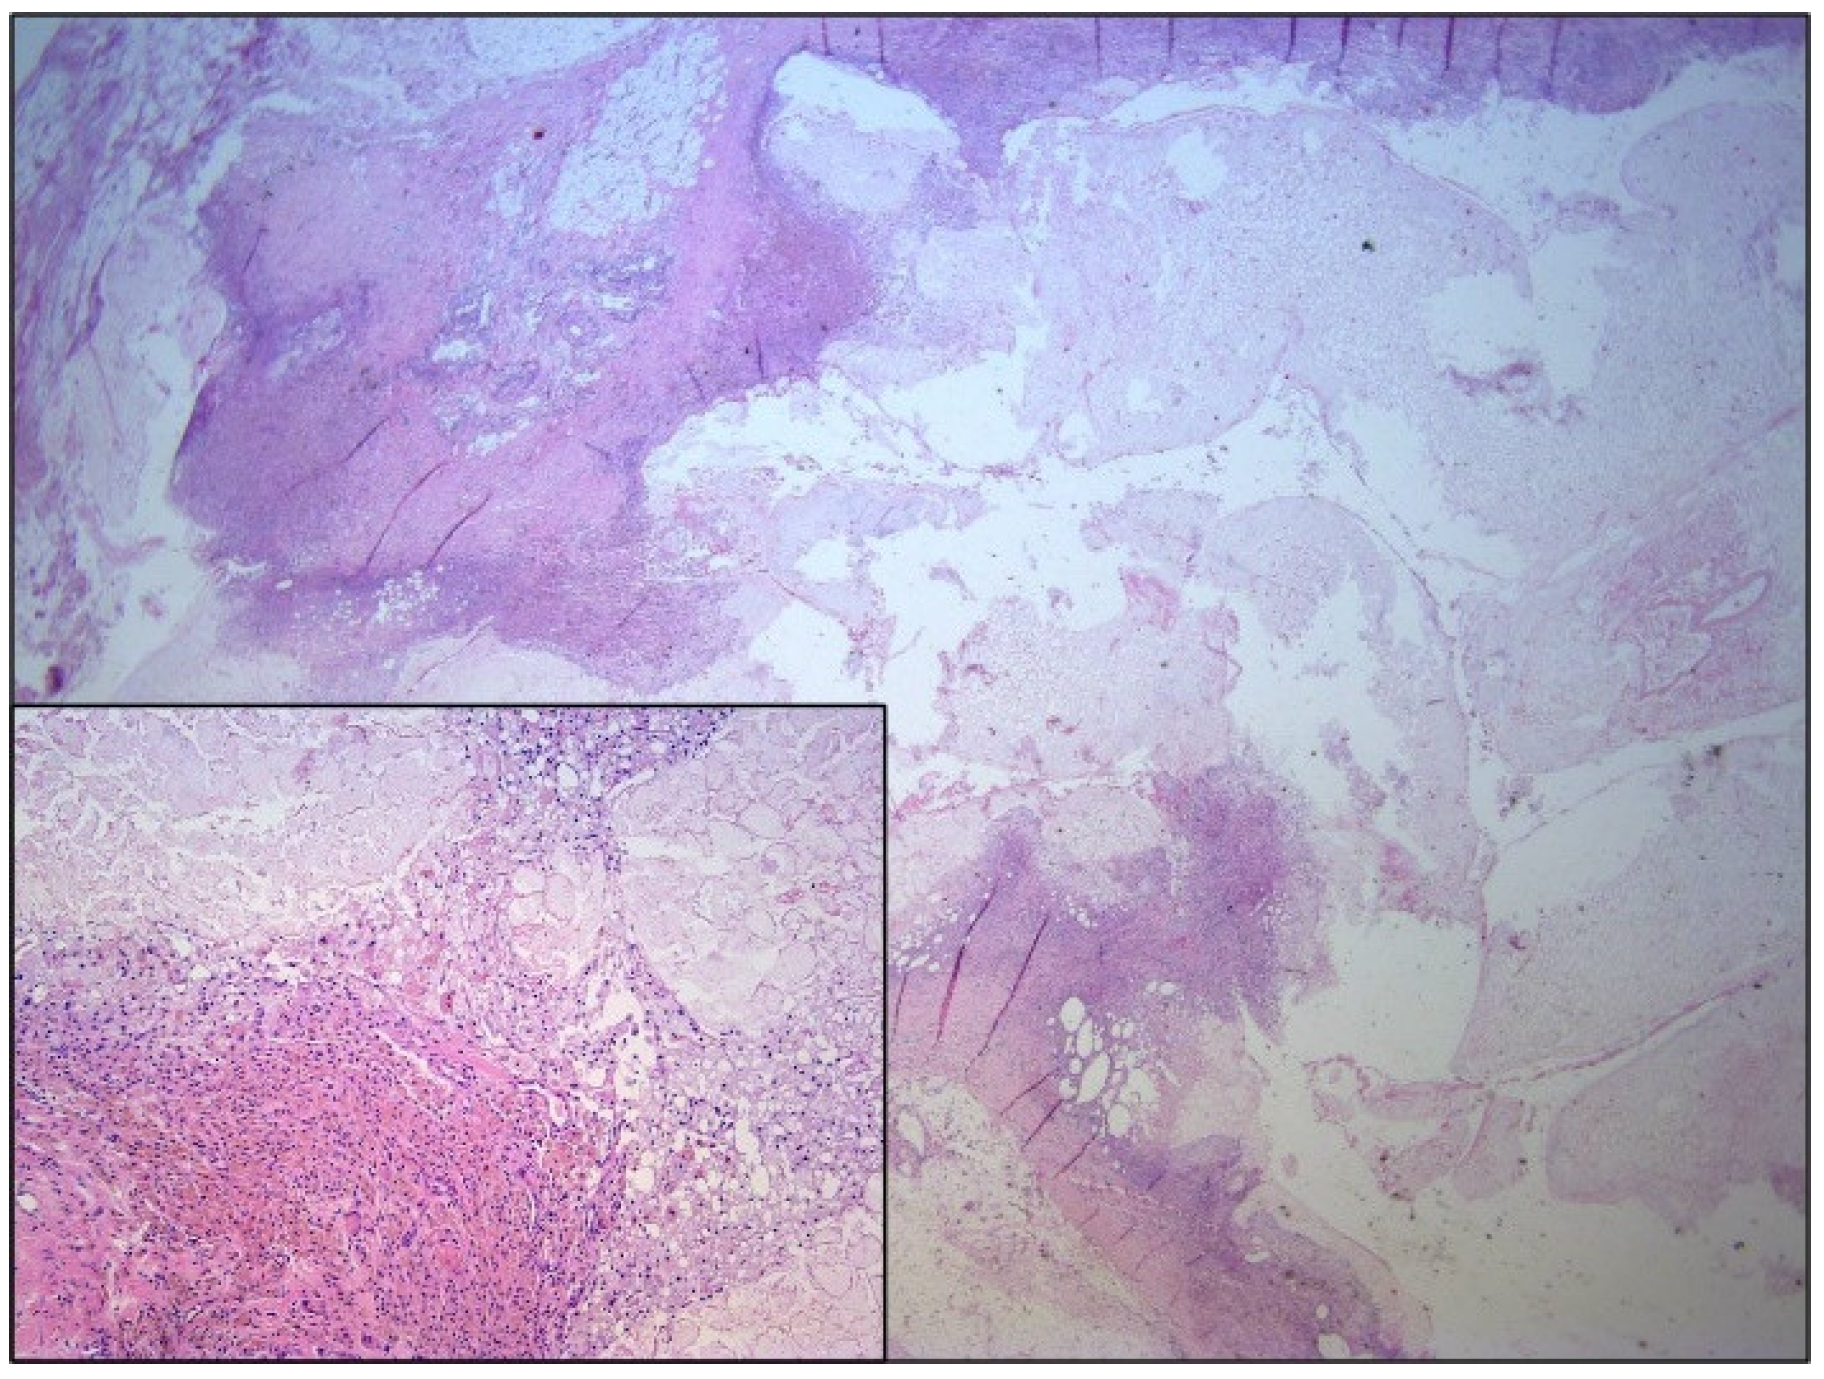

2. Case Report